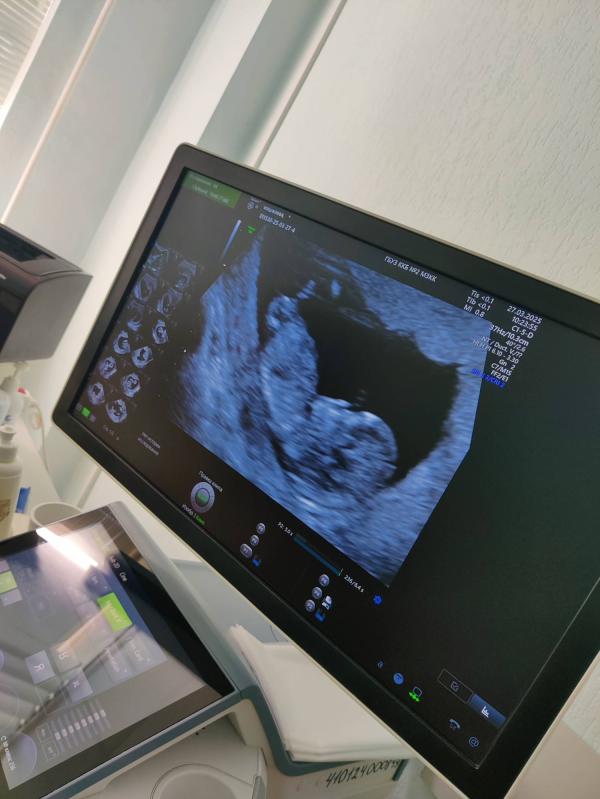

Первое узи, первый скрининг и казалось ещё столько времени....

Пролетело как один миг и вот ты с нами, сыночек 💙